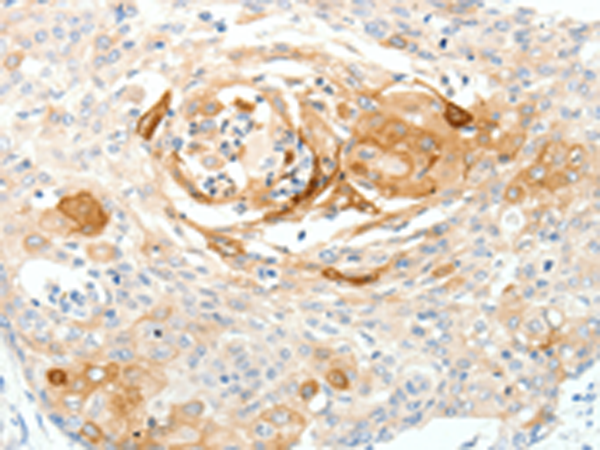

分类: 科研抗体货号: P11313别名: PDGF1, PDGF-A应用: IHC反应种属: Human, Mouse, Rat